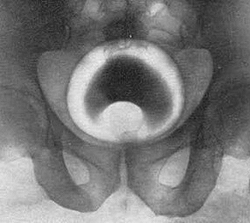

Врач-уролог проводит пальцевое исследование простаты. Для того, чтобы оценить выраженность симптомов аденомы простаты, больному предлагают заполнить дневник мочеиспусканий. Выполняют исследование секрета простаты и мазков из уретры для исключения инфекционных осложнений. Проводят УЗИ простаты, во время которого определяют объем предстательной железы, выявляют камни и участки с застойными явлениями, оценивают количество остаточной мочи, состояние почек и мочевыводящих путей.

Врач-уролог проводит пальцевое исследование простаты. Для того, чтобы оценить выраженность симптомов аденомы простаты, больному предлагают заполнить дневник мочеиспусканий. Выполняют исследование секрета простаты и мазков из уретры для исключения инфекционных осложнений. Проводят УЗИ простаты, во время которого определяют объем предстательной железы, выявляют камни и участки с застойными явлениями, оценивают количество остаточной мочи, состояние почек и мочевыводящих путей.

Достоверно судить о степени задержки мочи позволяет урофлоуметрия (время мочеиспускания и скорость потока мочи определяется специальным аппаратом). Для исключения рака предстательной железы необходимо оценить уровень ПСА (простатоспецифического антигена) величина которого в норме не должна превышать 4нг/мл. В спорных случаях проводится биопсия простаты. Цистография и экскреторная урография при аденоме простаты в последние годы проводятся реже в связи с появлением новых, менее инвазивных и более безопасных методов исследования (УЗИ). Иногда для исключения заболеваний со схожей симптоматикой или при подготовке к оперативному лечению выполняют цистоскопию.